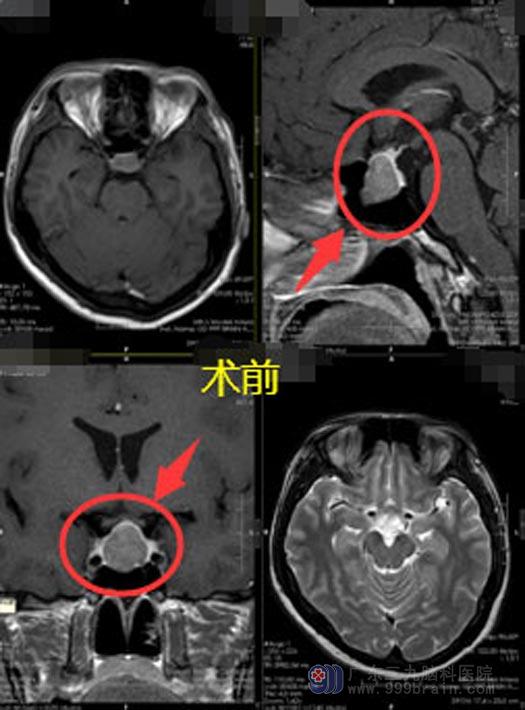

肢端肥大症的一线治疗是手术切除肿瘤,陈姐具有手术指征,由鲁明主刀在全麻下行内镜经鼻蝶鞍区垂体腺瘤切除术,肿瘤被顺利全切。

▲手术前